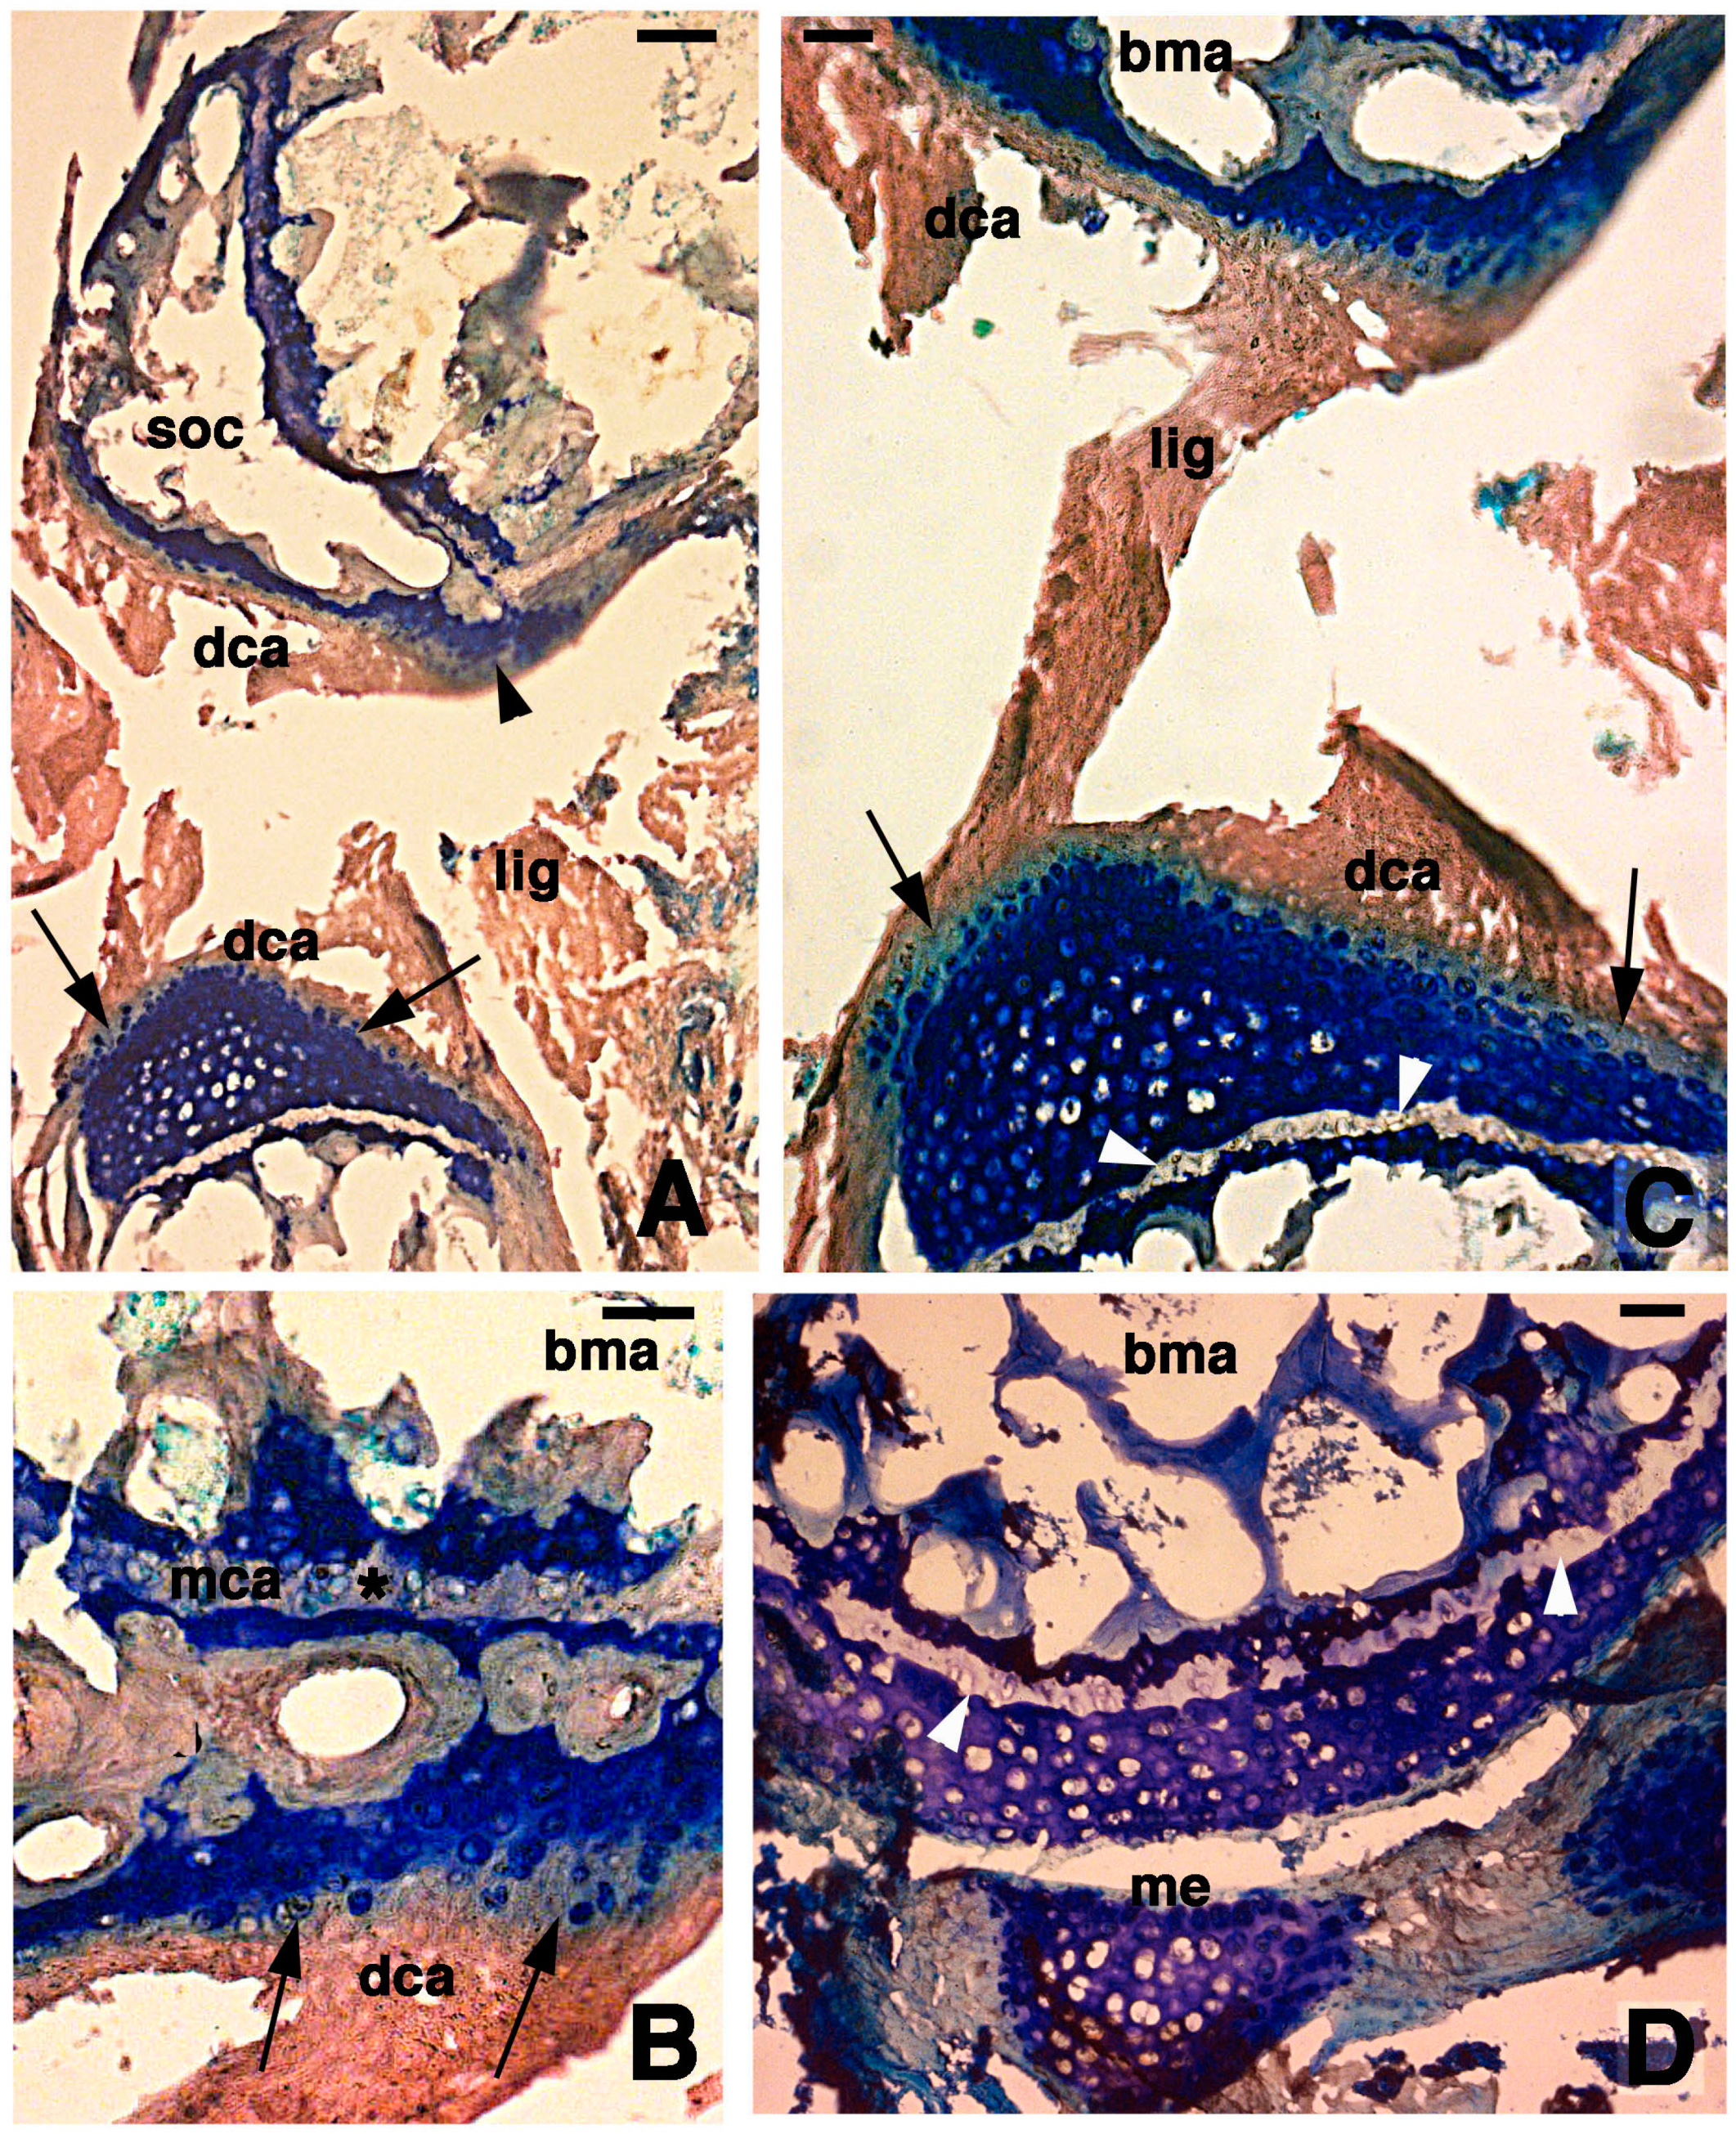

Figure 3.

Histological aspects of the knee 7 days after the lesion. (A) Degenerating articular cartilage surface of the femur (arrowhead) while a region of regenerating cartilage is seen in the tibia (arrows) localized beneath the degenerated and eosinophilic articular cartilage with fragments of ligaments/meniscus. Bar, 100 µm; (B) Detail of the degenerated femur eosinophilic cartilage, in continuation with degenerating (pyknotic) chondrocytes (arrows). Also part of the metaphyseal plate appears to be degenerating (asterisk). Bar, 50 µm; (C) Detail on the ligament connection between the regenerated tibia cartilage (arrows) and the degenerating cartilage in the femur. Bar, 25 µm; (D) Case showing regeneration in the articular cartilage of the femur although a region of degenerated and chromophobic cartilage is still present in part of the metaphyseal plate. Bar, 25 µm. Legends: bma, bone marrow; dca, degenerated cartilage; lig, ligament; me, meniscus; mca, metaphyseal plate; soc, secondary ossification center.

At 7 days post-lesion in some areas of the tibia and femur, there were regions of degenerated cartilage, just as there were at 4 days post-injury. Moreover, some areas with regenerating chondrocytes were seen (Figure 3A). The degenerated cartilage consisted in an outer eosinophilic tissue facing the sinovial cavity and in a still basophilic area containing groups of roundish chondrocytes (Figure 3B). The new cartilaginous tissue was formed by numerous roundish chondrocytes with scarce extracellular matrix and random disposition (Figure 3C). Chondrocytes tended to occupy most of the new articular cartilage, still largely covered by remnants of the external degenerated cartilage that were attached to the ligaments (Figure 3C,D). A line of flat chondrocytes, mimicking the superficial layer of a normal articular cartilage, was seen between the new basophilic cartilaginous cells and the degenerated eosinophilic cartilaginous tissue (arrows in Figure 3C). Also, the new cartilage formed numerous irregular layers of chondrocytes that tended to merge with the metaphyseal plate. In the latter only a thin pale layer, made of acidophilic or damaged chondrocytes with no basophilia, was visible between the new articular cartilage and the adjacent methaphyseal (growth) plate (Figure 3C,D). It also appeared that some cartilage regeneration also occurred in the meniscus.